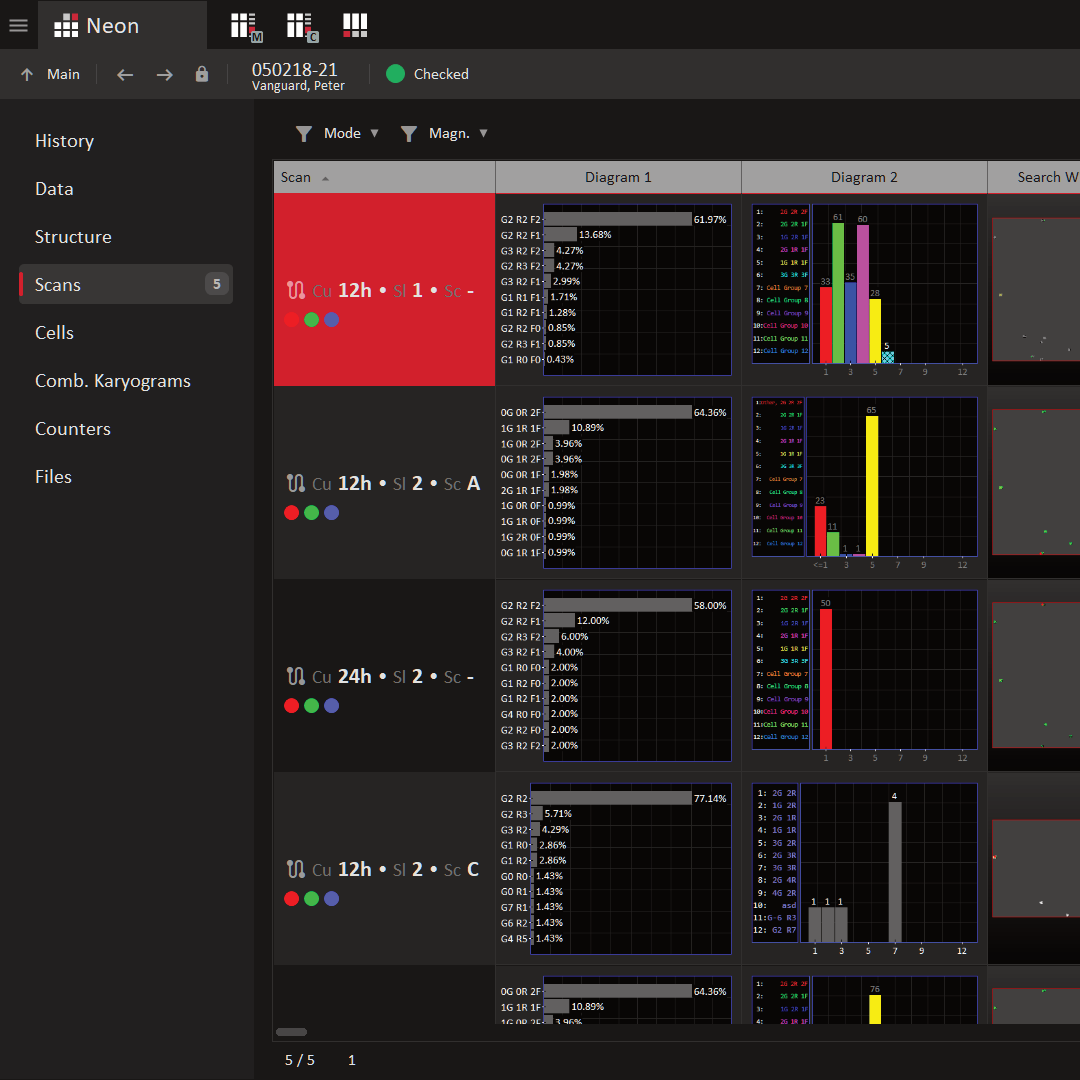

Metafer makes reviewing scanning results fast and easy, displaying all detected objects in a clear gallery linked to their slide coordinates for quick retrieval. Measurement details appear in the gallery or as intuitive charts for simple analysis and filtering. With the Neon accessory, users can organize images and findings, including data from Ikaros and third-party software, compile reports, and map complete workflows effortlessly.

All Records. Instantly Clear.

Metafer goes far beyond core software capabilities. Every installation comes with Neon, a powerful accessory that streamlines your data and workflow management - putting complete control at your fingertips. Every scan performed with Metafer, along with all detected objects, is automatically registered, indexed, and linked to the corresponding record, project, or case by Neon. As users interact with the images or records, Neon logs every action, ensuring full transparency and letting your team instantly see the current processing status.

Neon keeps your records organized and accessible. A clean, intuitive table summarizes key information for each record, while additional details such as metadata, user notes, or results are easily expanded when needed. Powerful, user-friendly search and filter tools make locating any record a matter of seconds. Records can also be sorted by status or urgency, and Neon seamlessly integrates with existing Laboratory Information Management Systems (LIMS) or other database software for smooth data import and export.